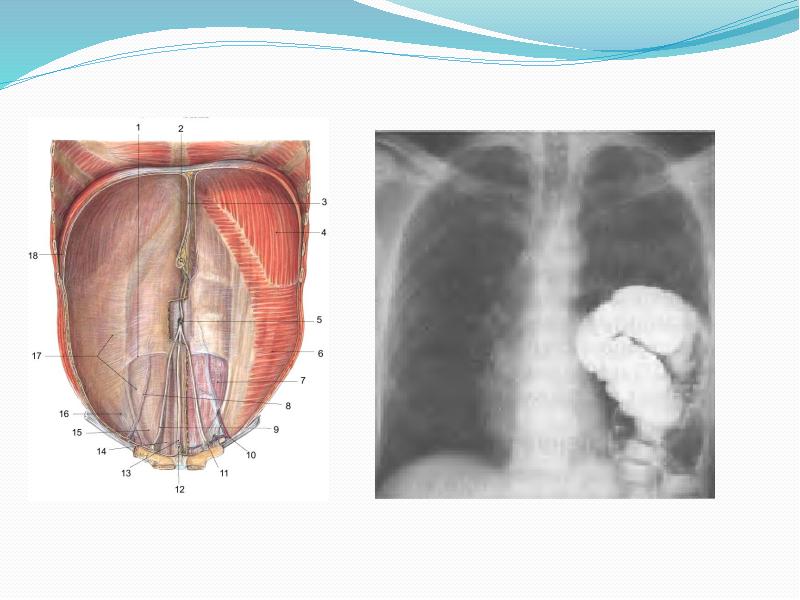

- 23. Инструментальды тексеру әдісі Рентгенологиялық тексеру (рентгенография, рентгеноскопия) Компьютерлік томография УДЗ